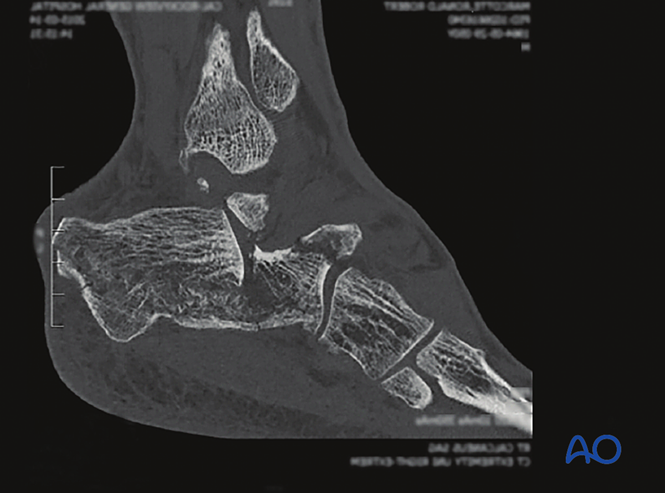

图示为严重创伤后3天的足部,此时不适合手术。